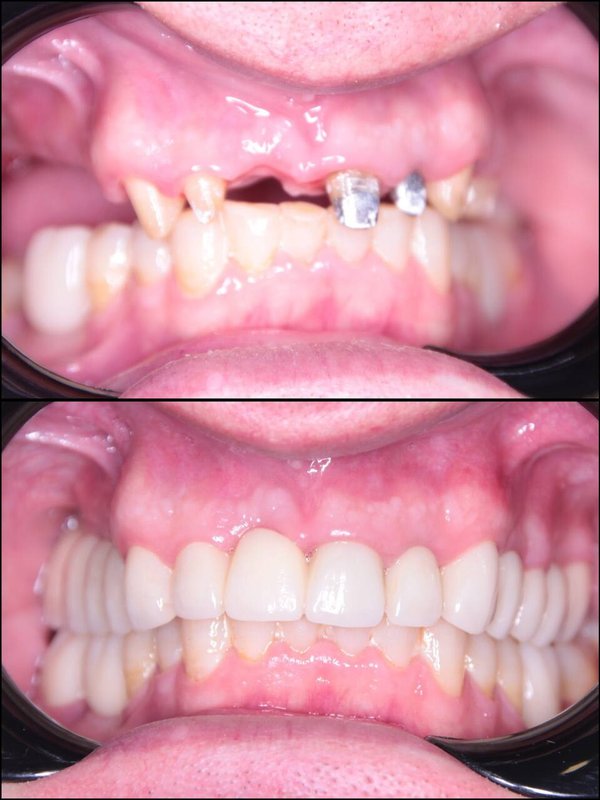

Фотогалерея